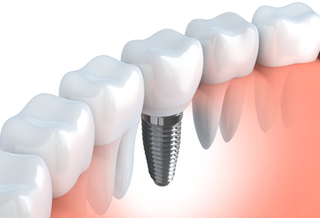

インプラントとは

虫歯や歯周病で歯を失ってしまった場合、人工の歯を挿入することで従来のようにお食事をすることができます。